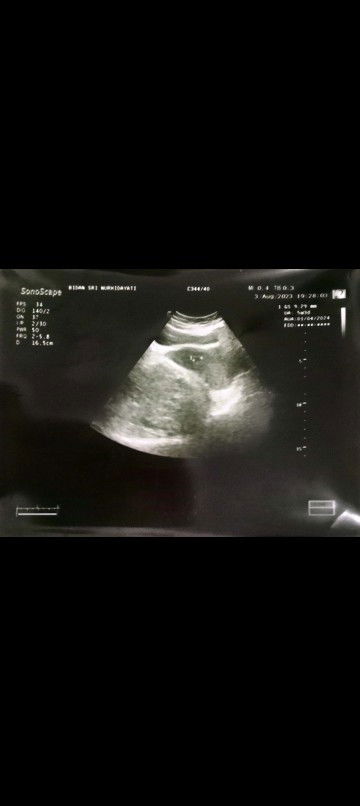

Hpht24 juni tp belum kliatan janin tidk ada kluhan flek atau kram perut ada yg prnah ngalamin ga

coba second opinion spog lain bun.. bisa trjdi jika siklus menstruasi bunda tdk teratur atau yg tipe siklus panjang( lbh dari 35 hr).. saya siklus menstruasi 32 hr an, hpht 29 juni, usg sudah uk 8 mggu 4 hr, sudah trlihat janin +dengar djj ..

Aku 6 minggu blm kliatan jg bun baru kantong aja, disuruh dtg 2 mingguan lagi hpht 17juli